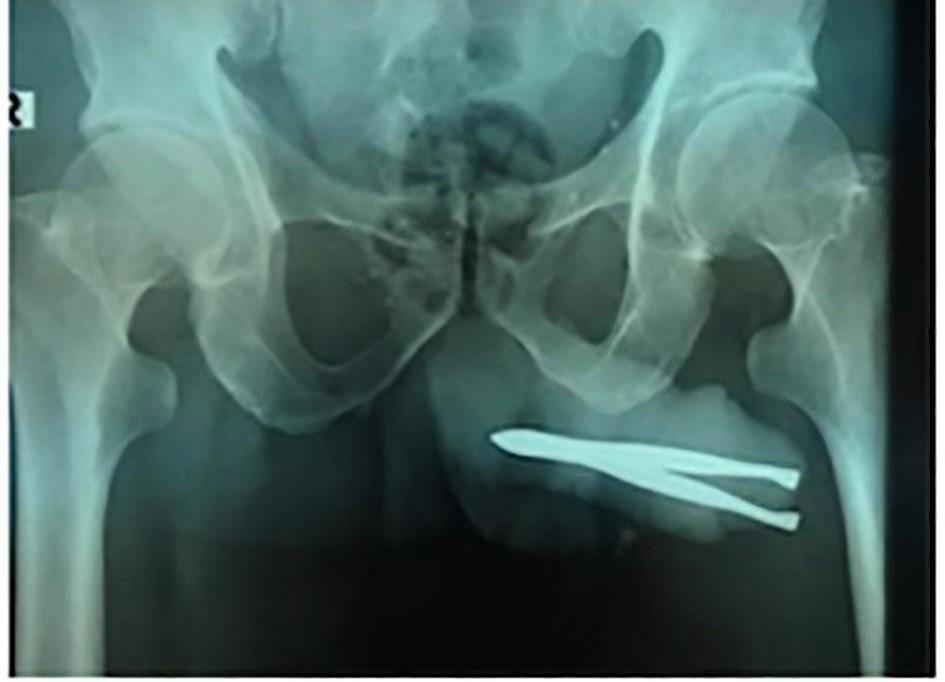

他照X光後,醫生驚訝地發現男子的陰莖裡竟塞了一把鉗子,且整把鉗子幾乎卡在體內。

印尼54歲男子的X光照,可見鉗子被卡在重要部位內。